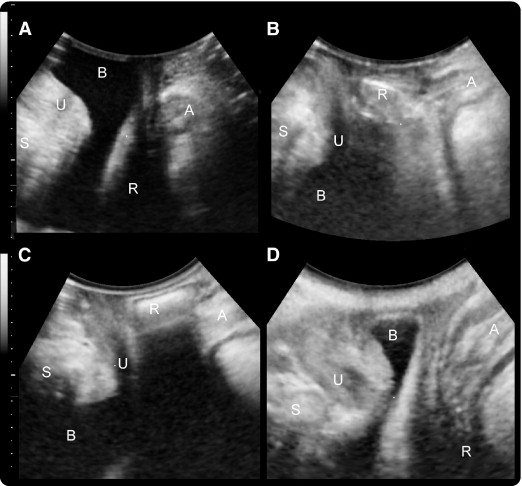

A transvaginal ultrasound is an internal scan of the female reproductive organs. It involves inserting a small ultrasound probe, called a transducer, into the vagina to produce incredibly detailed images of the organs in the pelvic region.

By comparison, a transvaginal ultrasound can provide more close-up images of the internal organs than an external pelvic ultrasound.

Once the transducer is in place, it produces sound waves that bounce off of the internal organs and relay information. To create a complete picture and bring different areas into focus, the sonographer or doctor rotates the transducer. This tool transmits the information directly to a screen.

The images display immediately on the screen, making it possible for the person and the healthcare professional to monitor the scan in real-time.